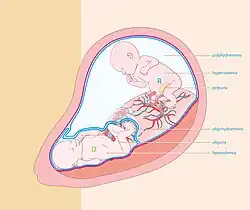

Twin-to-twin transfusion syndrome

Monozygotic twins who share a placenta can develop twin-to-twin transfusion syndrome. This condition means that blood from one twin is being diverted into the other twin. One twin, the 'donor' twin, is small and anemic, the other, the 'recipient' twin, is large and polycythemic. The lives of both twins are endangered by this condition.

Heterotopic pregnancy

Heterotopic pregnancy is an exceedingly rare type of dizygotic twinning in which one twin implants in the uterus as normal and the other remains in the fallopian tube as an ectopic pregnancy. Ectopic pregnancies must be resolved because they can be life-threatening to the mother. However, in most cases, the intrauterine pregnancy can be salvaged.